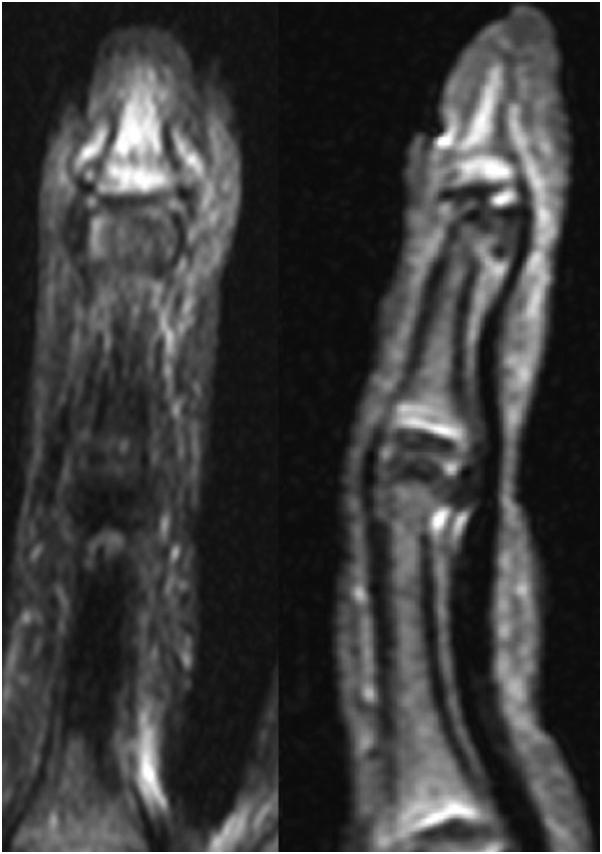

Seymour fractures are common injuries in the pediatric population. High rates of deep infection have been reported due to delayed presentation and subsequent treatment. This report describes the case of a 13-year-old male wrestler who presented 1 month after a finger injury that was later diagnosed as a subacute Seymour fracture with osteomyelitis. The patient underwent irrigation and debridement and fracture reduction stabilized with nonabsorbable suture fixation. After 6 weeks of intravenous antibiotics, the patient was recovering well, with radiographic evidence of fracture healing and clearance of infection. This case highlights the use of a single suture as a treatment option for fixation of unstable Seymour fractures with delayed presentation. The management of acute open distal phalangeal physeal fractures is well described in the literature; however, further investigations are warranted into the optimal management of chronically infected digits with unstable Seymour fractures.

西摩骨折是儿科人群中的常见损伤。据报道,由于就诊延迟和后续治疗,深部感染发生率很高。本报告描述了一名13岁男性摔跤运动员的病例,他在手指受伤1个月后就诊,后来被诊断为亚急性西摩骨折并伴有骨髓炎。患者接受了冲洗和清创,并采用不可吸收缝线固定稳定骨折复位。静脉注射抗生素6周后,患者恢复良好,有骨折愈合和感染清除的影像学证据。该病例强调了使用单根缝线作为延迟就诊的不稳定西摩骨折固定的一种治疗选择。文献中对急性开放性远端指骨骨骺骨折的处理有详细描述;然而,对于慢性感染且伴有不稳定西摩骨折的手指的最佳处理方法,仍需进一步研究。